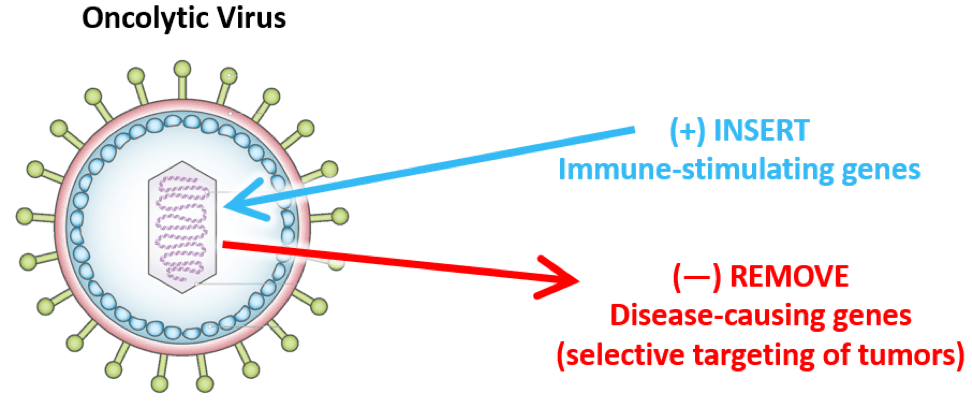

溶瘤病毒是一类具有复制能力的肿瘤杀伤型病毒,世界上最早出现溶瘤病毒的报道,是由于1912年的意大利一位宫颈癌患者感染狂犬病毒后,肿瘤随之消退。